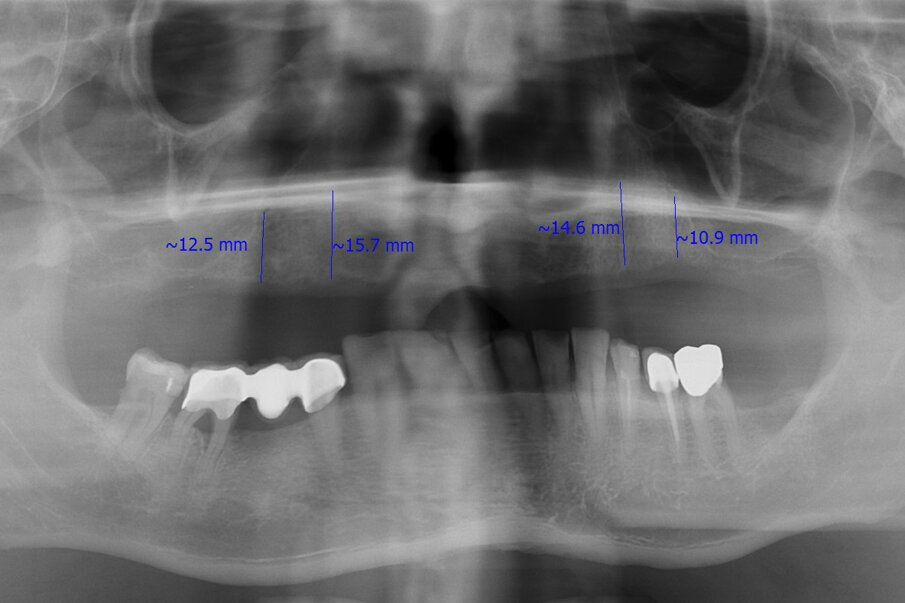

A 55-year-old male patient complained about the retention of his maxillary complete denture and requested a fixed solution. Intra-oral examination and radiography confirmed an edentulous maxilla (Figs. 1 & 2).

Fig. 2: Pre-op radiograph.